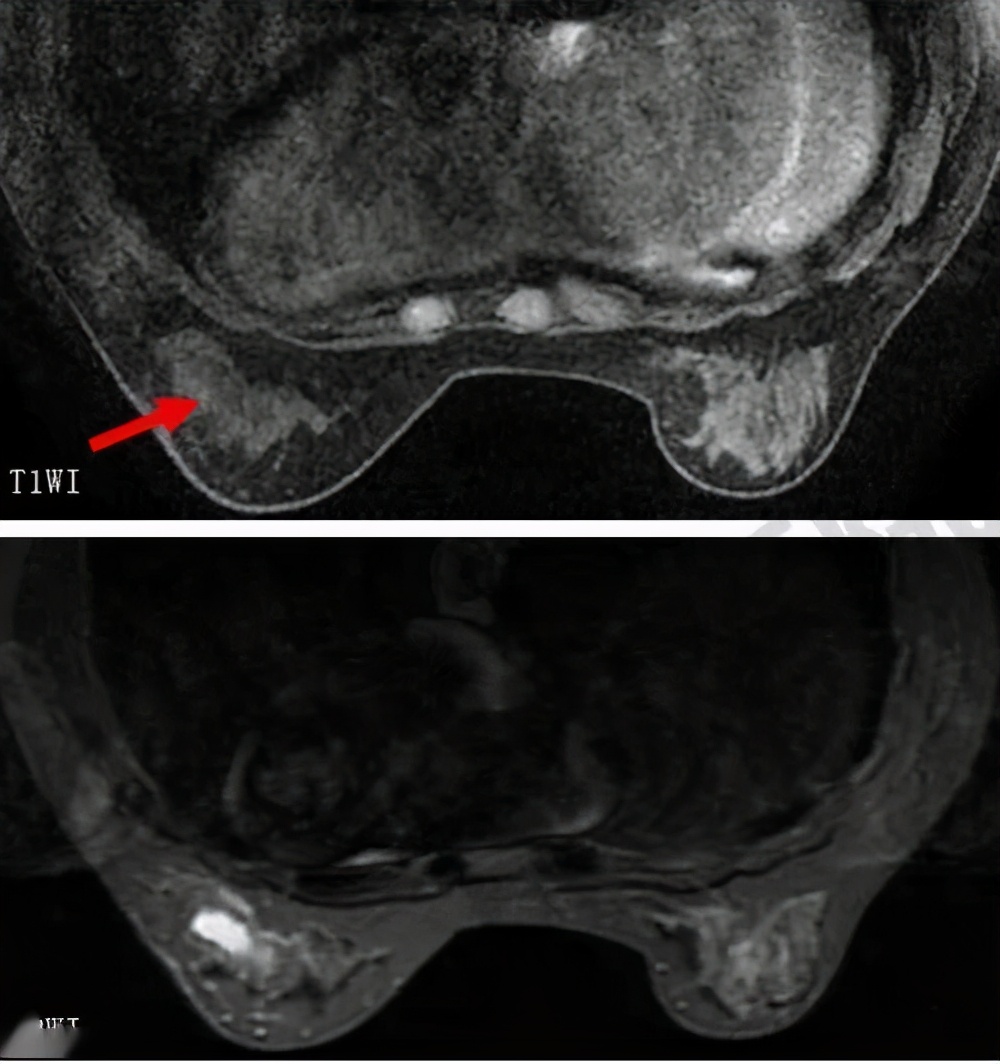

巫医生解读:4类病变需要进一步检查,需要引起重视。 这一类结节的患者比较多,切忌慌张,进一步检查,医院专科都是有办法明确的。 4类病变需要进行MR检查, 临床中遇到很多病变经过多学科检查,会降级。 如果肿块或者结节恶性可能性大,需要病例活检。恶性特征特别明显的检查完全身(包括淋巴结等等),必要时直接手术。患者切莫紧张,做完检查明确以后该怎么处理怎么处理,不要通过网上一查惊慌失措。